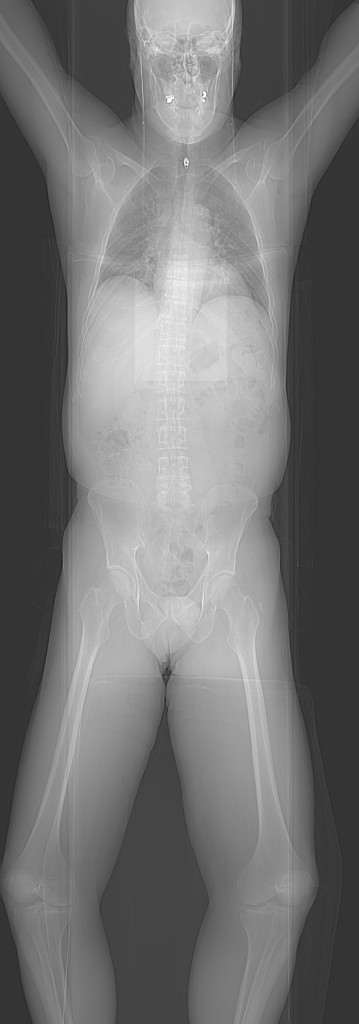

Yes that’s me in the pic